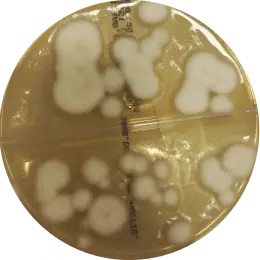

Microsporum gypseum

Scopulariopsis brevicaulisFot.

mgr Karolina Nowaczewska Pracownia Mikrobiologii, ALAB laboratoria Sp. z o.o.

mgr Przemysław Dziewirz Pracownia Mikrobiologii, Laboratoria Medyczne Grupa ALAB